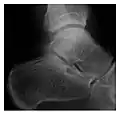

Fatigue fractures are more frequent in women which may be due to the relatively smaller bones of women. Moreover, pregnancy is a well-recognized risk factor for femoral neck fatigue fracture. While fibular and metatarsal fractures have a low risk of complications, other sites including the femoral neck, midanterior tibia, navicular, talar, and other intraarticular fractures are prone to complications such as delayed union, nonunion, and displacement. The site of the insufficiency fracture may be specific to the activity: for example, rugby and basketball players are more prone to navicular fractures, while gymnasts have a higher risk for talar fractures (Figure 7). Long distance runners are at increased risk for pelvic, tibial (Figures 8 and 9), and fibular fractures. In the military, calcaneus (Figure 10) and metatarsals are the most commonly cited injuries, especially in new recruits. Billiard players are at risk for upper limb fractures (Figure 11).[1]

Figure 7: Fatigue fracture of the talus in a 25-year-old male basketball player with right hind foot and ankle pain, without history of trauma, and a normal initial radiograph (not shown). (a) One-month followup lateral radiograph shows normal appearance. (b) Sagittal T1-weighted MRI shows an irregular fracture line (arrow) within an ill-defined area of hypointensity corresponding to bone marrow edema.[1]

Figure 10: Calcaneal fatigue fracture in a 30-year-old male runner. Radiographs were normal (not shown). (a) Sagittal T1-weighted and (b) short tau inversion recovery images show a linear hypointensity (arrows) of calcaneal tuberosity within diffuse bone marrow edema, which appears as an ill-defined area of hyperintensity on a fluid sensitive pulse sequence (arrowheads).[1]